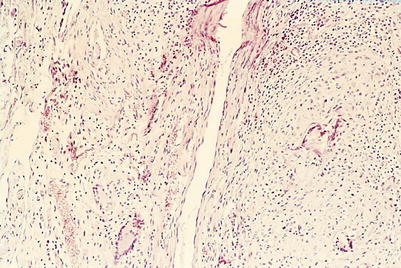

Between day 14 and 60 random investigations by electron microscopy were performed.

During weeks 3 and 4, a neointima started from the adjoining intact duct to cover the whole inner surface of the transplants. Blood capillaries grow in the vessel wall toward the neointima.

Between days 40 and 60, within the wall caverns appeared, together with a massive infiltration of activated lymphocytes, plasma cells, macrophages, and erythrocytes. The wall however remained stable because of the new endothelium and the subendothelial tissue containing a continuous basal membrane, structured collagen fibers type I, and differentiated muscle cells (Figs. 2.14, 2.15, and 2.16).

Fig. 2.15

Allogeneic abdominal thoracic duct graft of rat. 40 days after grafting (scanning electron microscopy, 440-fold magnification). LU lumen, EN endothelium, cF collagen fibers, Faden suture)